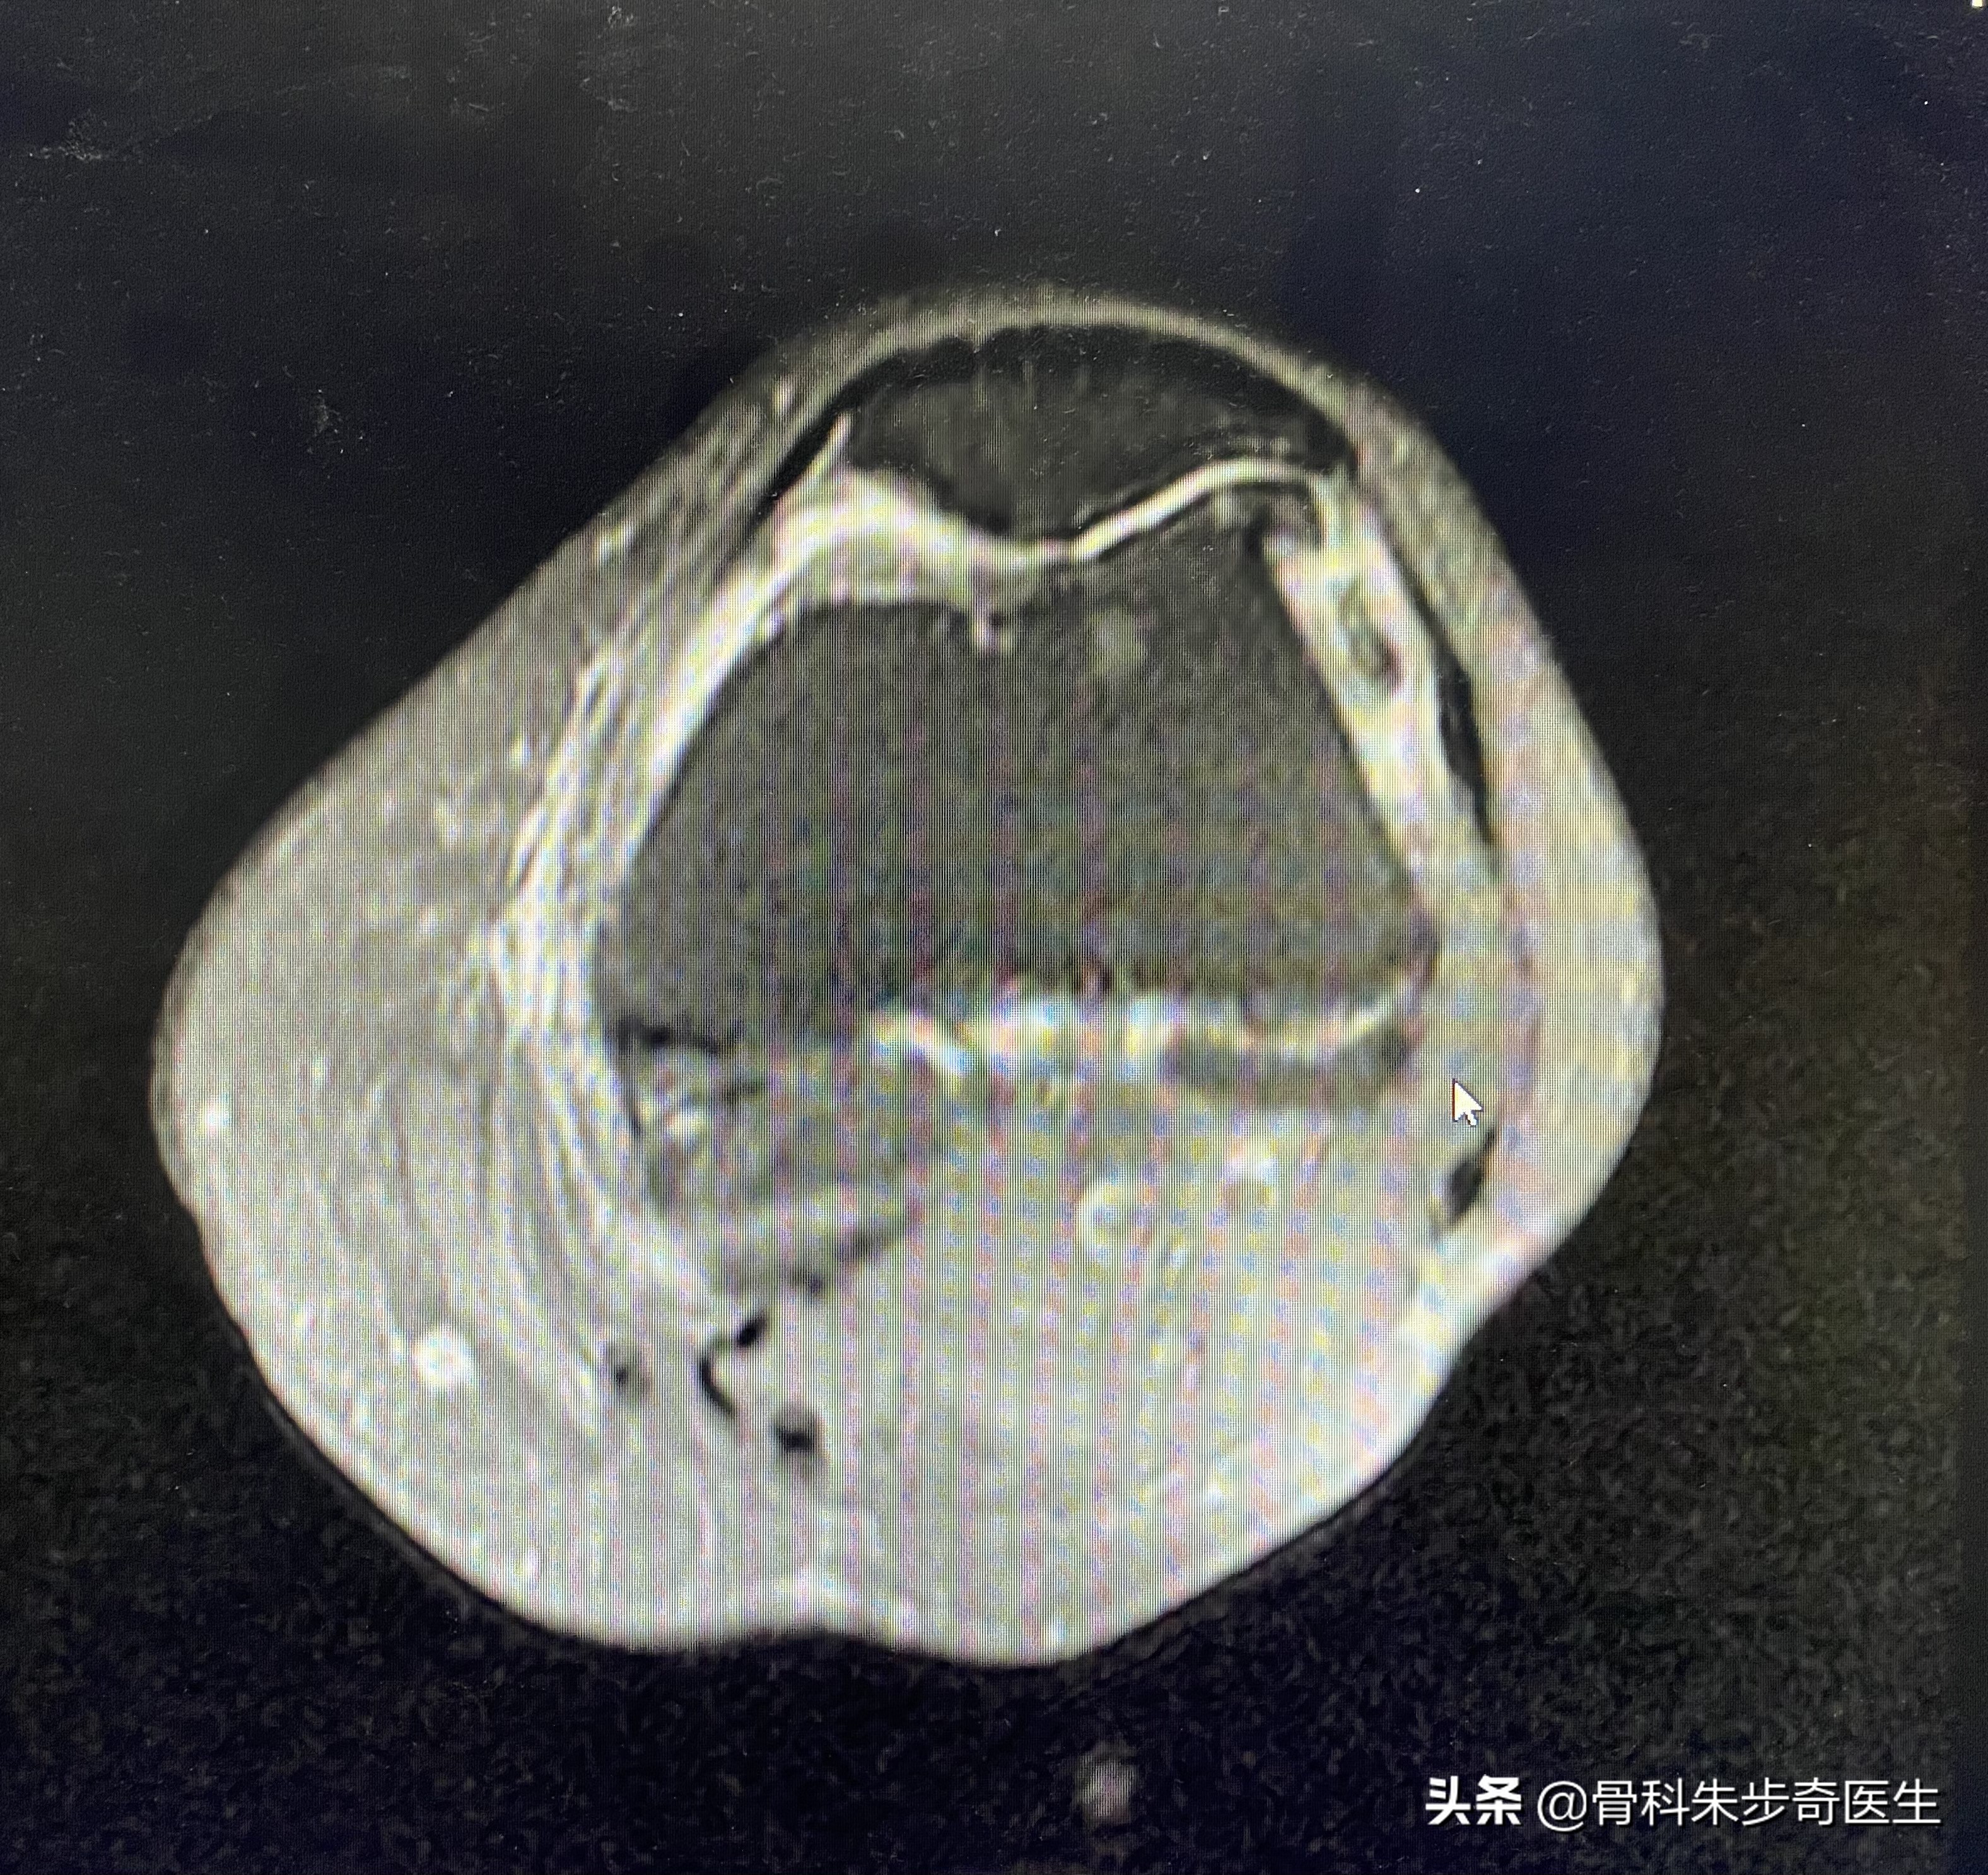

住院之后为了进一步搞清楚膝关节内部的问题,又做了一个核磁共振,结果如下:

看起来问题挺多,其实不管是软化,还是半月板撕裂,游离体,滑膜增厚,这些其实都是关节退变的表现。

根据这个情况,比较适合的是关节镜治疗,需要用关节镜把游离体取出来,同时观察膝关节内部的软骨,和滑膜情况,还可以清理一下内部的关节,所以建议她做膝关节的关节镜。